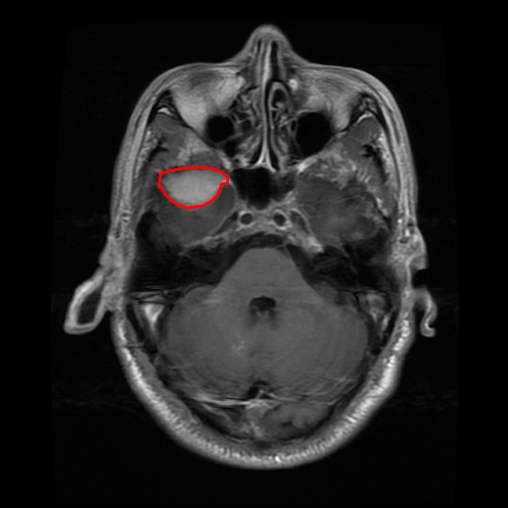

From the above discussions, we have discovered the significant potential of applying Retinex theory to image segmentation and explored its fundamental differences from traditional models. Traditional image segmentation models typically focus on the impact of intensity information on the segmentation results. Therefore, when faced with complex segmentation scenarios, the segmentation results are often affected by lighting, artifacts, and unclear boundaries in the image. As shown in Fig. 1, we present the results of the classical local model LIF [ZHANG20101199] for segmenting brain tumor images along with surrounding tissue edema. The irregular ring-like enhancement caused by the edematous tissue leads to irregular boundaries and low contrast in the images. Consequently, the LIF model can only identify the central necrotic and liquefied regions of the tumor, failing to detect the boundaries and becoming trapped in local minima. In this paper, we draw inspiration from the Retinex theory, which is widely applied in the field of image enhancement. According to Retinex theory, the reflectance component characterizes the intrinsic structural properties of the observed image and preserves texture information independent of illumination variations. By integrating this reflectance component into the level set framework, our model achieves robust segmentation of medical images even under severe intensity inhomogeneity. In addition, a linearized Structural-Prior is proposed to restore intensity consistency and capture local geometric features, thereby improving boundary localization in complex or blurred regions. Furthermore, a relaxed binary level set representation is employed to enhance robustness against noise and to enable accurate tracking of complex contours. Based on these innovations, we propose a novel variational reflectance-based level set model (RefLSM) that simultaneously corrects bias fields and performs segmentation. Experimental results demonstrate that RefLSM significantly outperforms conventional level set methods in both segmentation accuracy and robustness. We present the results of our model segmenting the two brain tumor images mentioned above in Fig. 2.

To address the challenge of segmenting images with severe intensity inhomogeneity, we propose a linearized structural prior that directly operates on the reflectance component . Reflectance-based structural information is more robust to illumination variations and bias field distortions, helping preserve weak edges and subtle anatomical boundaries. As shown in Fig. 2, our method can accurately delineate tumor boundaries and surrounding edema even under severe inhomogeneity, where traditional intensity-based models often fail. The proposed prior aligns smoothed reflectance gradients with data-driven directions, enhancing inter-region contrast, preserving weak edges, and stabilizing the evolution of . Formally, we define the linear structure operator as the gradient field of the smoothed reflectance: